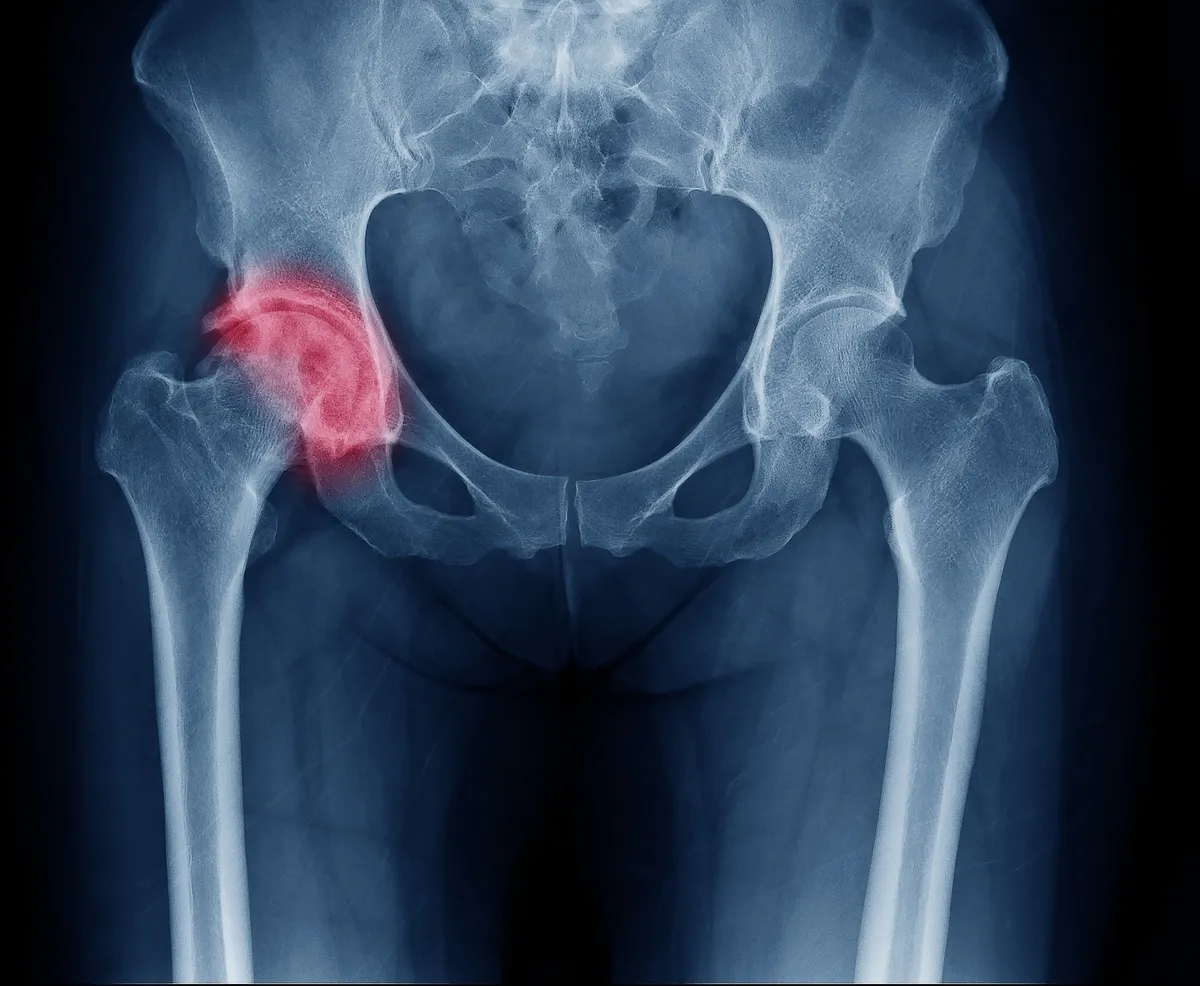

ارتباط مستقیم آرتروز لگن و درد مزمن چندموضعی

نتایج این مطالعه بسیار پیشگامانه بود؛ چراکه براساس آن به طور قطع مشخص شد که آرتروز لگن یک اثر علّی بر درد مزمن چندموضعی دارد. این یافته جنبهای از درد مزمن مرتبط با آرتروز را که قبلاً مورد بررسی قرار نگرفته بود آشکار میکند و راههای بالقوه برای درمانها و مداخلات هدفمندتر را روشن میکند.

علاوه بر این، این مطالعه روابط جذاب دیگری را کشف کرد. مشخص شد که درد مزمن چندموضعی روی زانو، لگن، دست و آرتروز کلی اثر دارد. این نشان دهنده یک تداخل چندوجهی بین درد مزمن و زیرگروههای مختلف آرتروز است. جالب توجه است که افسردگی و خستگی بر آرتروز زانو و دست تأثیرات علّی دارند؛ اما بر آرتروز لگن تأثیری ندارند.

پیامدهای این تحقیق عمیق است. این نه تنها درک ما را از رابطه پیچیده بین آرتروز و بیماریهای همراه افزایش میدهد، بلکه راه را برای رویکردهای مؤثرتر و متناسبتر برای مدیریت درد مزمن در بیماران آرتروز هموار میکند. این یافتهها نویدبخش توسعه درمانها و مداخلات هدفمند با هدف کاهش بار درد مزمن چند موضعی در افراد مبتلا به آرتروز لگن است.